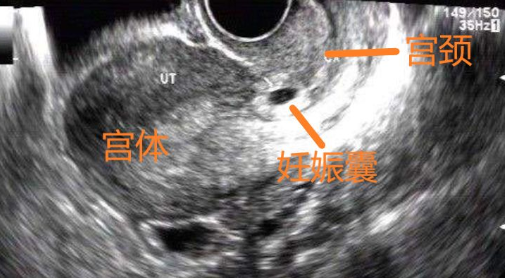

明確妊娠部位非常重要,應避免忽略性宮頸妊娠,行人流術導致陰道大出血危及生命安全。

宮腔鏡下進行胚胎清除術或吸取術。在進行操作時,可明確胚胎著床部位和胚胎大小,在直視下完整清除胚胎,并有效止血。但只適用于胎囊小,陰道出血不多,血hCG輕度升高者。